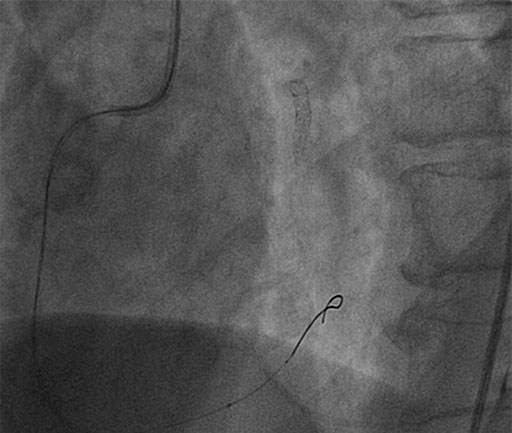

IVUS Guided RCA Assessment

• IVUS reveals MLA of 3.2mm2

• COMET™ wire re-connected

• FFR of 0.88, PCI not necessary of RCA

non significant FFR 0.88